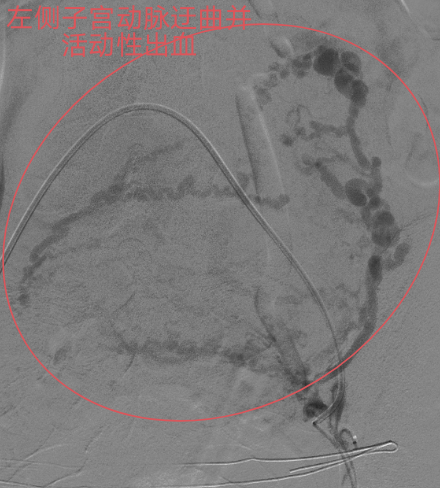

本着“生命至上”的原则,吴主任立即启动介入导管室为产妇施行“造影术”检查,造影发现产妇子宫动脉远端均有活动性出血,尤以左侧子宫动脉出血明显,血液不断外渗,病情紧急,止血治疗迫在眉睫!要知道产后大出血是非常凶险的疾病,不能有效止血可能需要切除子宫保命的!但患者才不到三十岁呀,正值青春年华,切除子宫对患者以后可是有非常大的影响。此时,能及时止血救命,又能保住子宫的微创介入止血法的优势就出来了!在患者及其家属的期盼和高度信任下,吴主任顺利为患者施行微创介入止血手术,术后患者子宫动脉出血停止,阴道出血减少,术后无需继续输血血压、血红蛋白均能维持稳定。术后经常规产后康复护理治疗后,患者病情稳定,没有异常阴道出血,现已康复出院。

血管造影见

双侧子宫动脉出血